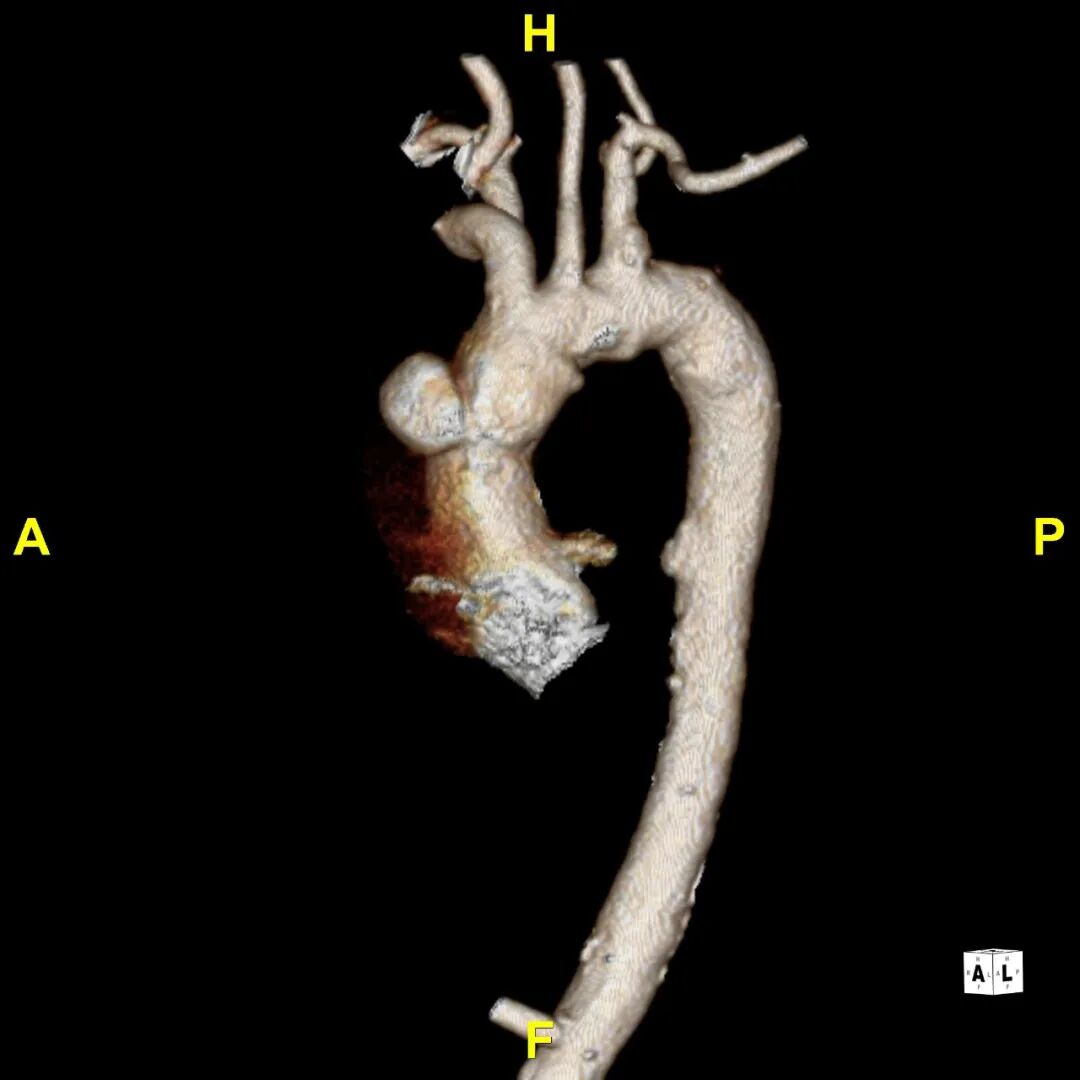

患者入院后行CTA检查,可见患者升主动脉巨大溃疡伴血肿,弓降部多发溃疡。无名动脉前缘至窦管交界大弯侧95.3mm,小弯侧54.7mm。

gore医疗怎么样「胸有乾坤」异“区”同“功” 精准定位——GORE® TAG® 可主动调控胸主动脉覆膜支架治疗升主动脉穿透性溃疡病例报道_https://www.jmylbn.com_新闻资讯_第7张

术前CTA

术前3D重建